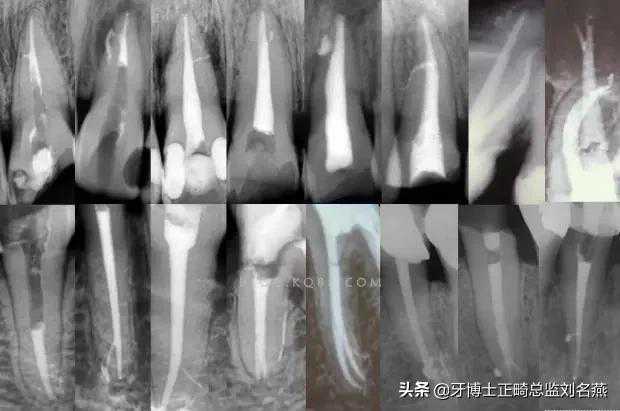

3、感染控制决定成败

根管治疗中感染控制的彻底程度直接决定根管治疗的成功率,对主根管、牙本质小管、侧支根管的控制同等重要。

完善根管治疗后的换牙失败主要原因是根管系统的顽固的感染或根尖周顽固的根管外细菌感染,当然也有可能是非细菌性因素,但根管内的感染占主要原因。

在高效率的机械预备根管时,一定要用专用的侧方开口针头的注射器大量多次的冲洗根管,次氯酸钠要加热后使用,并及时补充新鲜的液体到根管系统。

EDTA液体的使用可以很好去除根管预备中产生的玷污层,1%的CHX液体可以在30秒内杀灭粪肠球菌,并且有延缓作用,是优秀的终末冲洗液。

超声荡洗清理根管的效果要优于手工冲洗,很多医生考虑次氯酸钠的浓度,其实次氯酸钠冲洗液的浓度并不重要,重要的是冲洗的时间和次数,更换新鲜液体的频率和液体是否加热。

4、敢于否定自己

有些病例看上去似乎是完美的,但是患者就是感觉有明显的不适感,就应该考虑是否有未处理的根管内感染区域,分析是根管、峡部、分支、缝隙等原因后就要及时的采取措施。

失败病例的处理方法选择非手术再治疗还是手术再治疗,一般首选非手术再治疗,但要评估再治疗的预期结果,如果非手术再治疗的对患牙的创伤太大或预期效果不确定就考虑手术再治疗,全面考虑分析后决定方法。要及时的决定下一步的处理方法,长期的反复的复诊观察是没有意义的,最后的结果是流失患者。